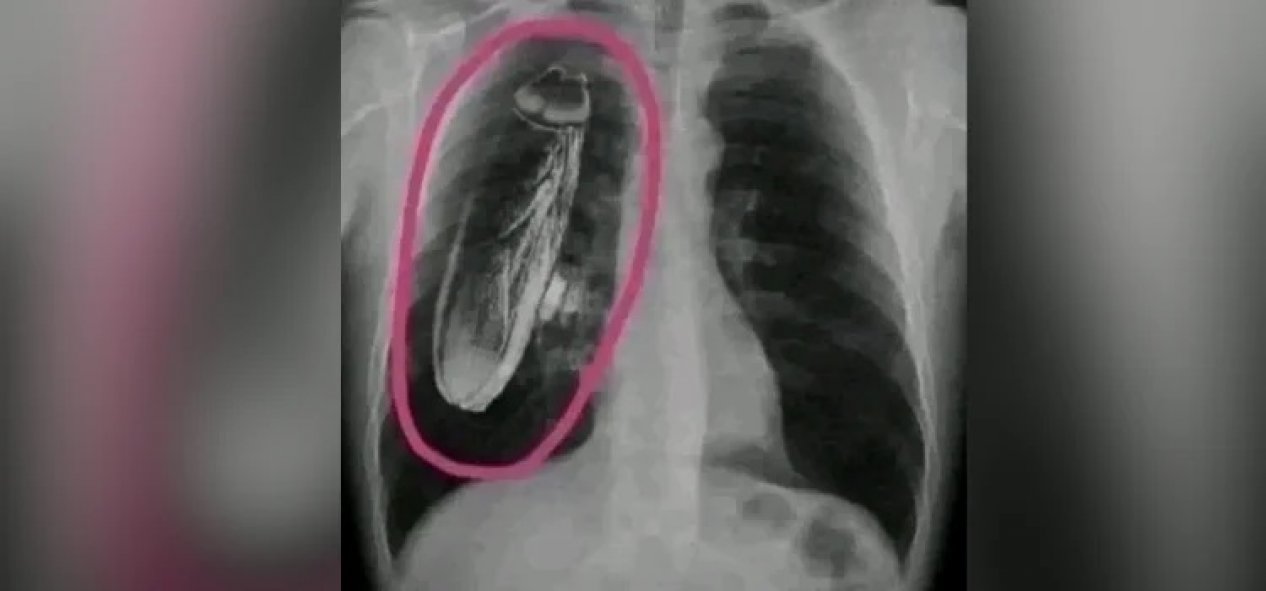

Sosyal medyada paylaşılan bir fotoğrafla Kenya’da bir hastanın göğüs röntgeninde hamam böceği görüldüğü öne sürüldü. İddiaya göre hasta, tedavi için Singapur'a kadar gelmiş ve Kenya’daki hastanenin yanıldığını, hamam böceğinin akciğerlerinde değil, röntgen cihazında olduğunu öğrenmiş.

İddiaya eklenen fotoğraf tersine görsel arama yöntemiyle arandığında, “hamam böceğinin” fotoğrafa sonradan eklendiği anlaşılıyor. Fotoğrafın aslı standart bir göğüs röntgeni.

İki görsel karşılaştırıldığında, böceğin sonradan eklendiği de görülüyor.

Anahtar kelimeler ile açık kaynaklardan yapılan aramalara göre de böyle bir olay kaydedilmemiş. Ayrıca, böcek görüntüsünün aktarıldığı gibi büyük olması bilime ve hayatın olağan akışına da aykırı.